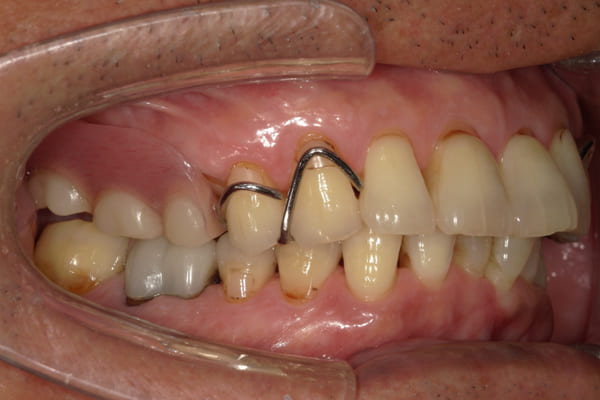

上の前歯が重度歯周病により動揺し、残せない状態のため、入れ歯も動揺がありました。

ご自身の歯に負担の少ないバネ、また見た目も改善

ご自身の歯に負担の少ないバネ

銀歯からセラミック歯に

バネをかける歯は繋げることで強度を増し、歯への負担を軽減し、歯の寿命を長くする設計へ。

バネがかかる歯の被せ物は、歯への負担を減らし、入れ歯が動きにくいようになる形態をあらかじめ付与することで、より入れ歯の機能が高まります。

治療を行う際、被せ物や入れ歯は、別々に考えるのではなく、一口腔単位としてお口全体のことを考え最良の治療計画を立てることが歯の寿命、機能効果を向上させるため、専門医としてこのことは常に心掛けて治療を行っています。

残りの歯に負担がかからないよう、被せ物と入れ歯の一体化を図った入れ歯

治療前は上下奥歯の入れ歯が削れていることで、かみ合わせが低くなり唇もつむった状態でした。

かみ合わせを適切な高さに戻したことで、本来の自然な口元へ。